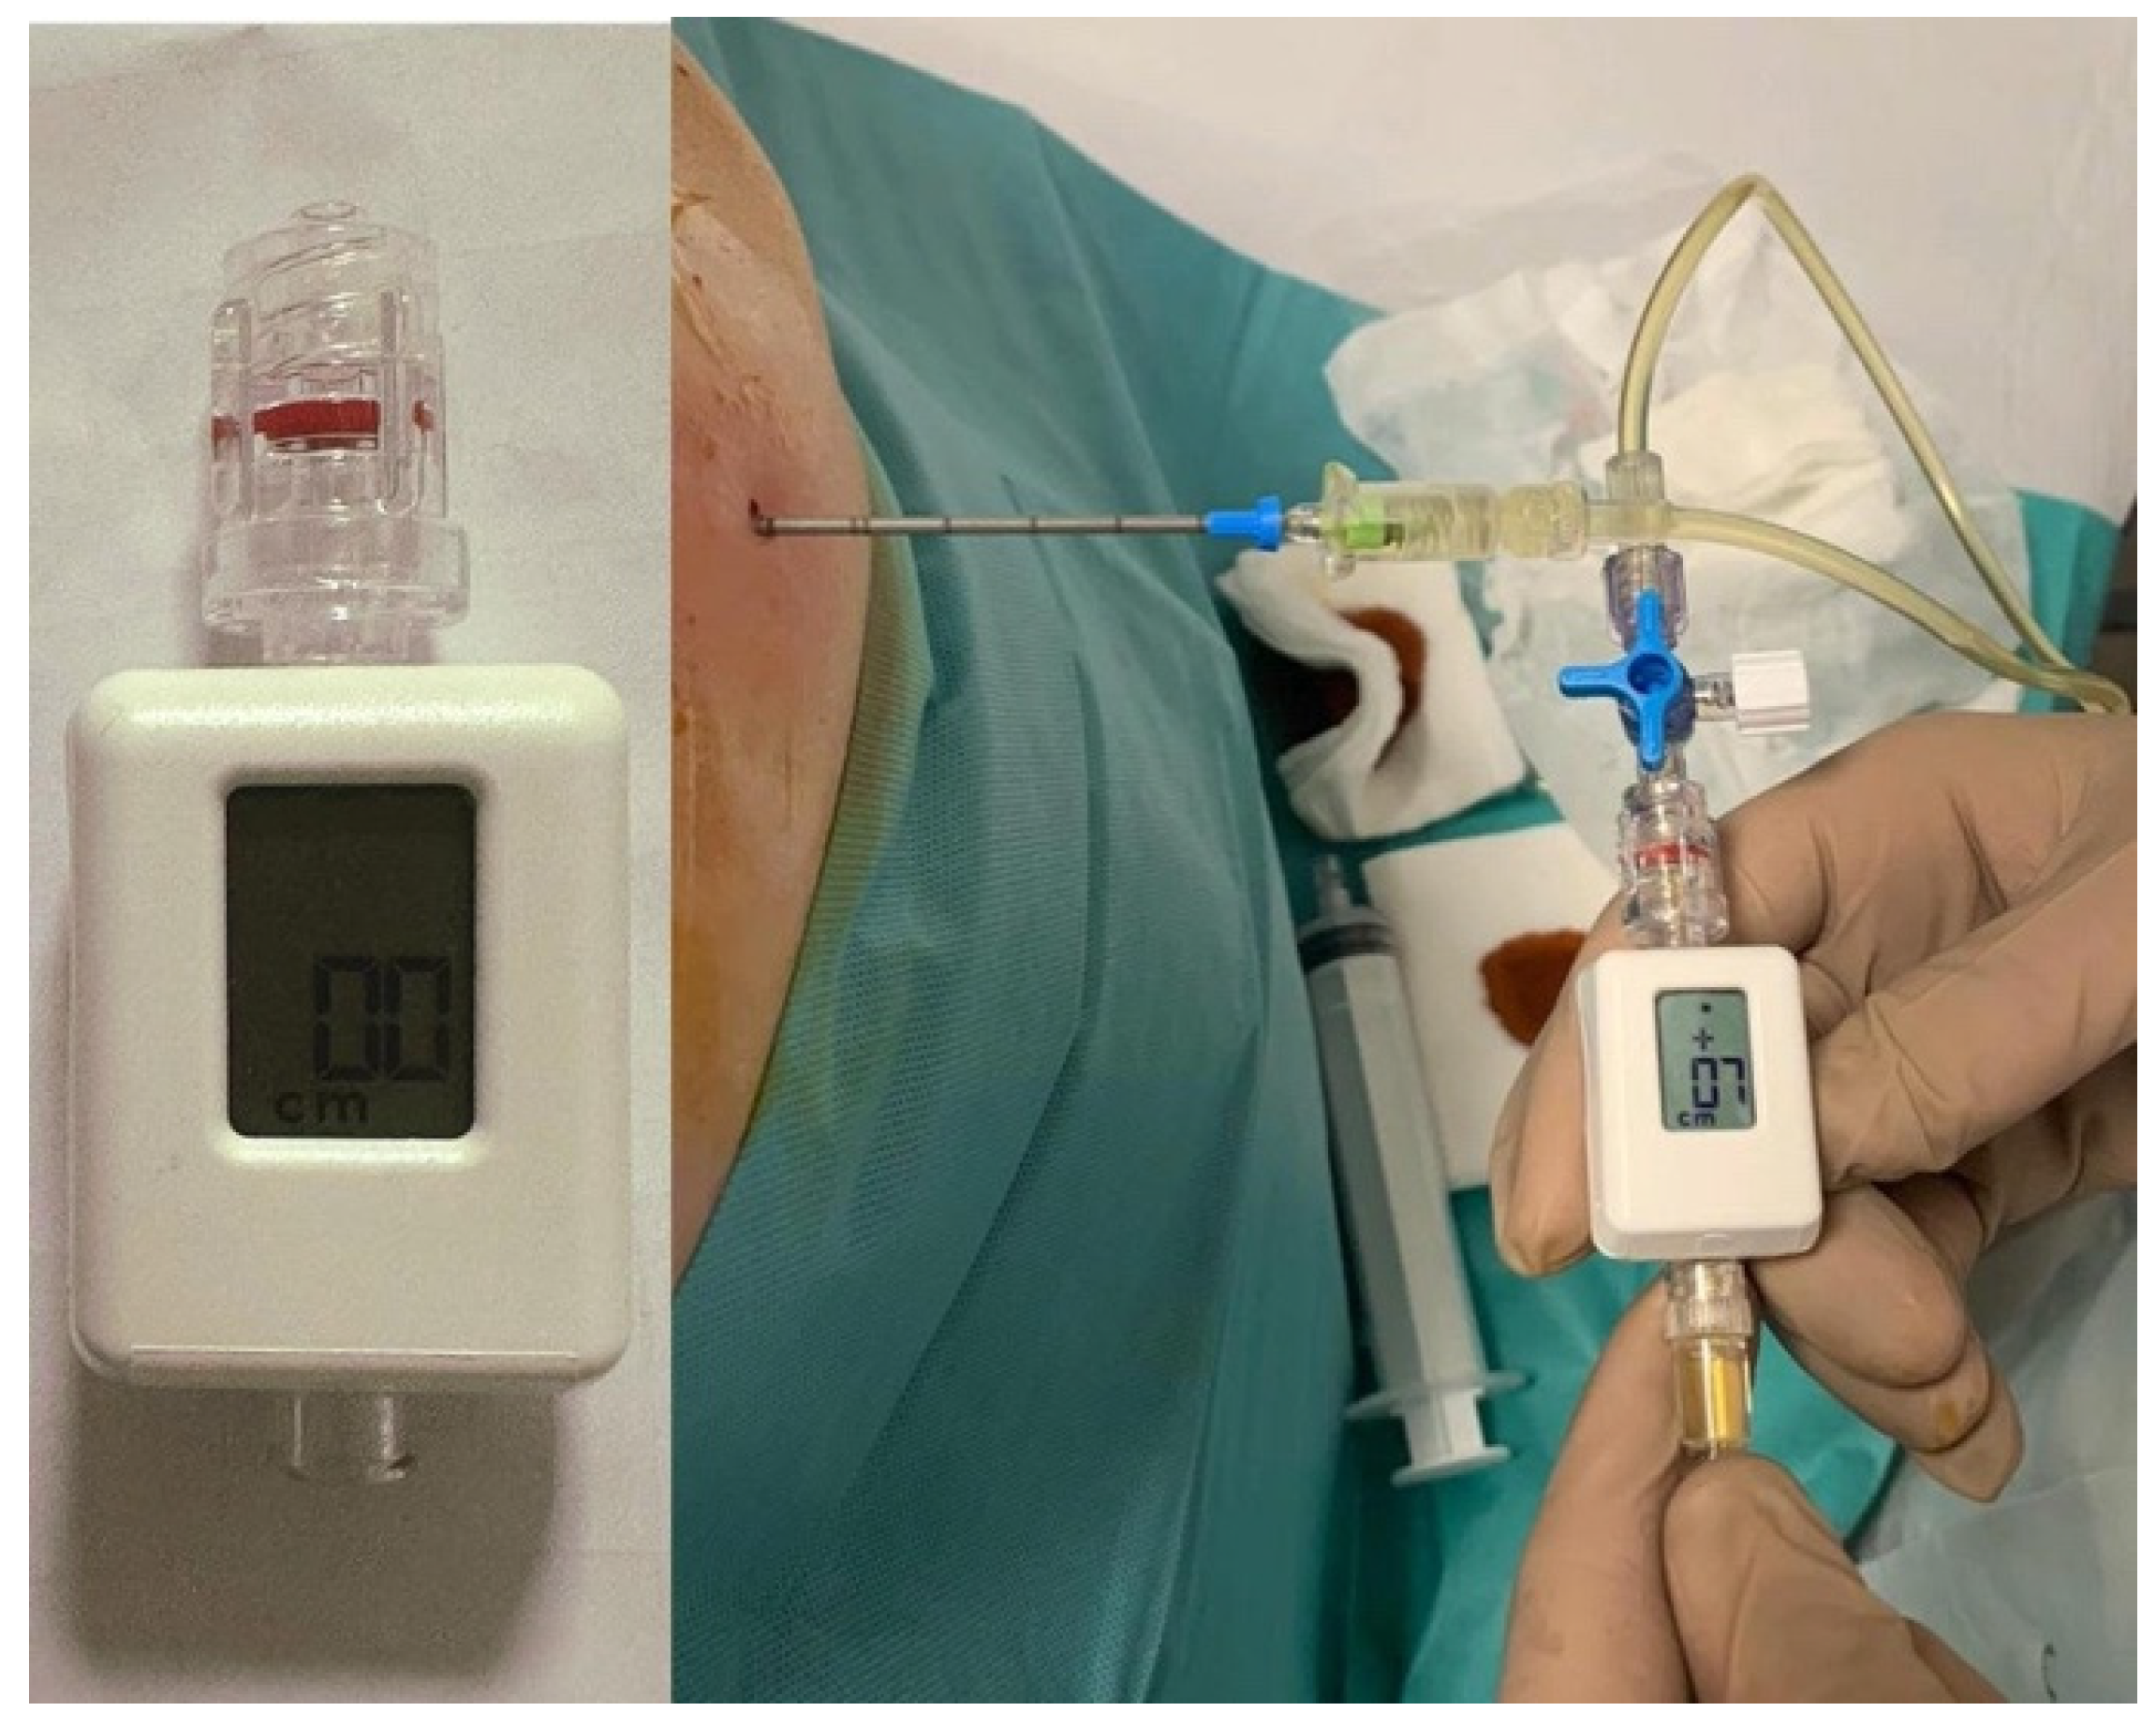

4.2. Pleural Manometry

- Faber, K.; Krenke, R. Pleural Manometry—Basics for Clinical Practice. Curr. Pulmonol. Rep. 2021, 10, 111–120. [Google Scholar] [CrossRef]